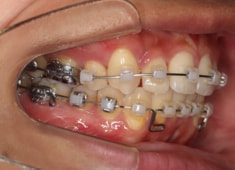

治療開始から24ヶ月後